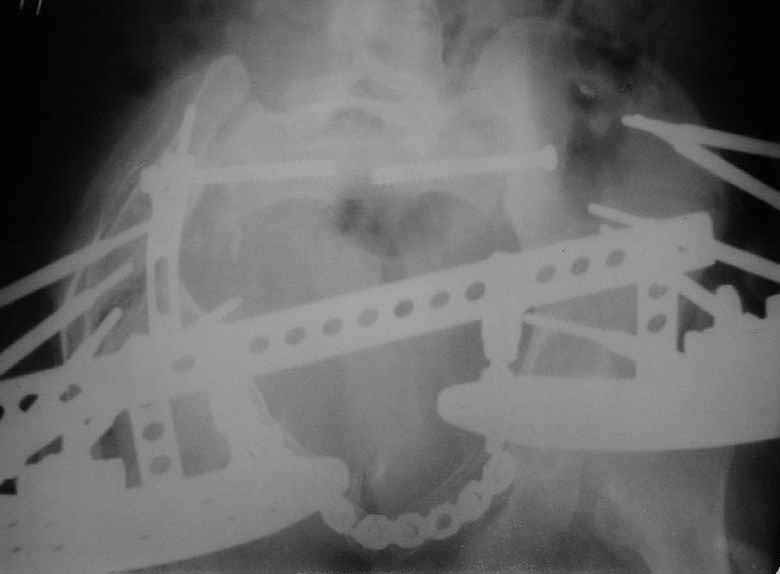

X-rays and more CT - see attached.

![]() |